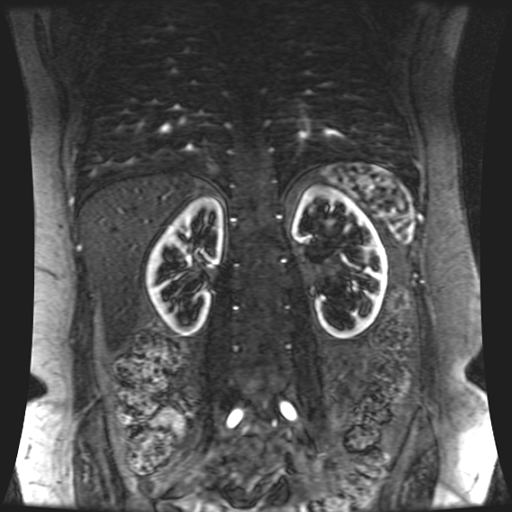

Paciente de sexo femenino, de 45 años de edad, refiere infecciones urinarias a repetición, no hay dolor, no refiere trauma, consulta por ardor al orinar, medico tratante le solicita resonancia abdominal, con énfasis en riñones, además un estudio de angiorenal.

Se prepara a paciente para ingreso a zona 4 del área de resonancia. Se coloca a paciente en decúbito supino, se canaliza en vena antecubital, se utiliza bobina de abdomen de 16 canales, se adquieren localizadores en tres planos, luego se procede a adquirir imágenes en diferentes planos, con secuencias echo spin y eco de gradiente, potenciadas a T1 y a T2.

Los sistemas colectores del riñón derecho y del riñón izquierdo, muestran alteración de sus calices primarios y secundarios, mostrando dilatación, la pelvis renal y el uréter se observan de características normales lo que indica que no hay proceso obstructivo.

Se observa dilatación del sistema calicial sin proceso obstructivo compatible con una anormalidad del desarrollo de los sistemas colectores de ambos riñones, definiéndose como una “megacaliosis”